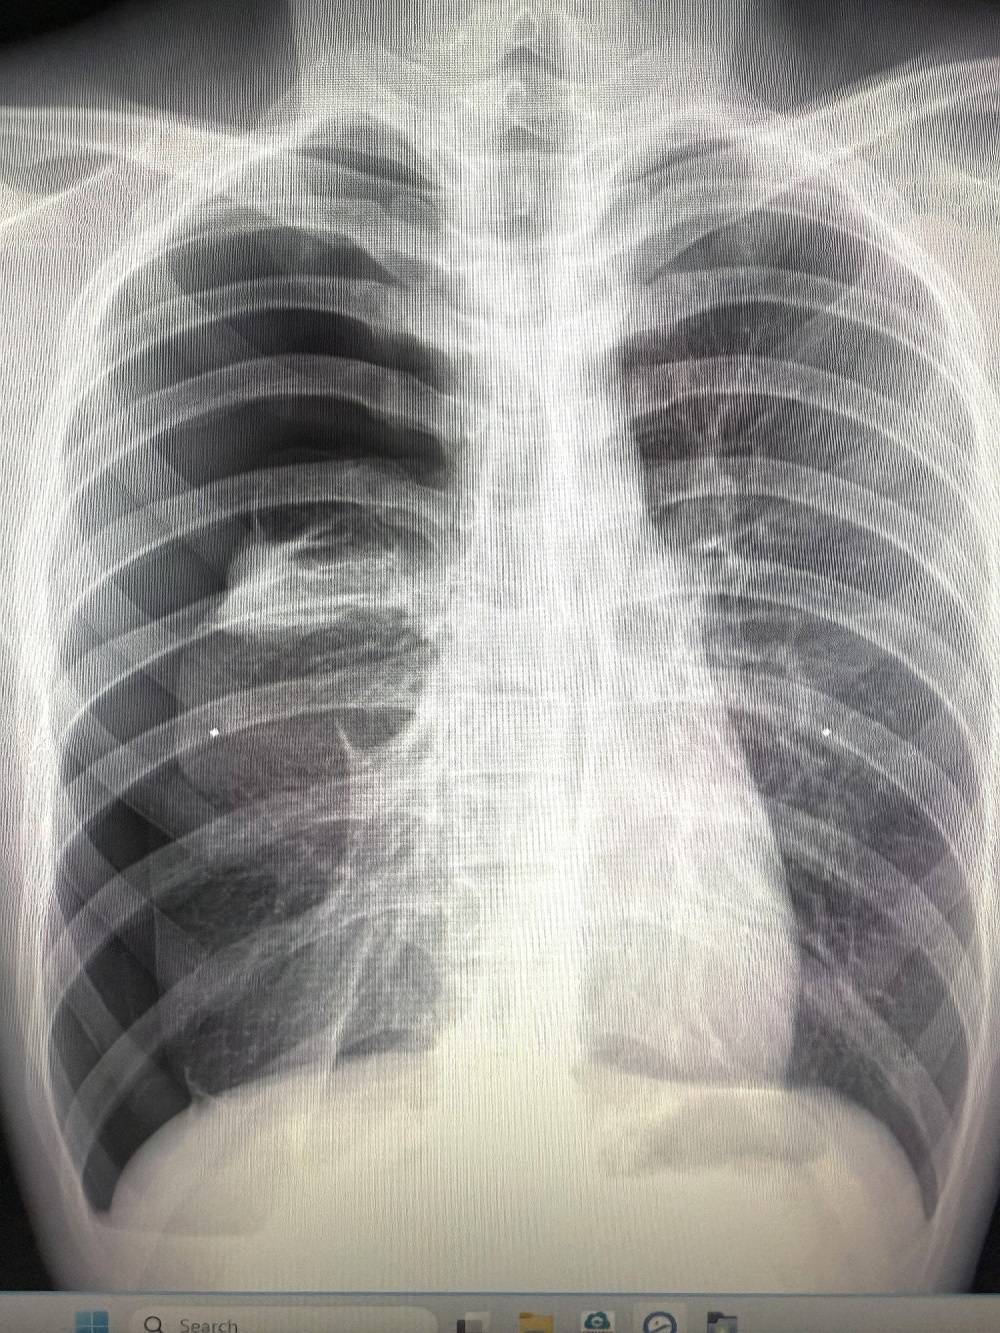

เมื่อไม่นานมานี้ ผมได้เจอเคสผู้ป่วยหญิงอายุราว 40 ปี มารักษาด้วยอาการเจ็บแน่นหน้าอก เป็น ๆ หาย ๆ อยู่หลายครั้ง แต่ไม่รู้สึกเหนื่อย รู้สึกว่าเมื่อมีอาการเจ็บหน้าอกทุกครั้ง มักจะเป็นในช่วงขณะมีประจำเดือน จึงมีอยู่ช่วงหนึ่งมีอาการเจ็บหน้าอกมากจึงรีบมาพบแพทย์ที่โรงพยาบาล หลังจากการตรวจสอบเอกซเรย์ พบว่าเป็นโรคลมรั่วในเยื่อหุ้มปอด ซึ่งมีโอกาสเสียชีวิตสูงหากไม่ทำการรักษา จึงรีบรับการรักษาตัวเข้าโรงพยาบาล

ซึ่งโดยปกติแล้วโรคลมรั่วในเยื่อหุ้มปอดจะมีจาก 3 สาเหตุ ได้แก่ 1) เกิดขึ้นได้เอง (Spontaneous Pneumothorax) มักเกิดในคนที่มีอายุน้อย ผอม สูง, 2) เกิดจากอาการมีโรคร่วม (Secondary Pneumothorax) พบในผู้ป่วยที่มีภาวะถุงลมโป่งพอง, 3) ลมรั่วขณะมีประจำเดือนที่เกิดจากช็อตโกตแลตซีสต์กระจายมา (Endometriosis Migration) โดยโรคลมรั่วขณะมีประจำเดือนนั้น โอกาสการเกิดโรคนี้ค่อนข้างยาก พบเจอไม่บ่อยมากนัก ผู้ป่วยเพศหญิงส่วนมากมักมาด้วยสาเหตุด้วยลมรั่วในปอดราว 20-30 % โดยภาวะลมในเยื่อหุ้มปอดชนิดนี้ เจอในเฉพาะเพศหญิงช่วงอายุ 32-37 ปีโดยอาจจะสัมพันธ์กับช็อตโกแลตซีสต์ในช่องท้อง หรือ มดลูกหรือ ไม่ก็ได้ โดยสาเหตุการเกิดของโรคนั้นยังไม่แน่ชัด ทั้งนี้อาการที่เกิดมักจะสัมพันธ์กับประจำเดือน ส่วนมากมักจะมีอาการเจ็บแน่นหน้าอกหรือหายใจไม่สุด ในบางครั้งอาจมีอาการเหนื่อย โดยมักจะเป็นในช่วง 24-72 ชั่วโมงนับตั้งแต่เริ่มมีประจำเดือนมาในวันแรก รศ.นพ.ศิระ เลาหทัย แพทย์ผู้เชี่ยวชาญศัลยศาสตร์ ทรวงอกเฉพาะทางด้านการผ่าตัดส่องกล้องในช่องทรวงอก โรงพยาบาลวชิรพยาบาล กล่าวว่าจากการวินิจฉัย ส่วนมากการทำ X-Ray หรือ ทำเอกซเรย์คอมพิวเตอร์ (CT Chest) หรือ MRI อาจพบได้ แต่อย่างไรก็ตามยังไม่มีการตรวจใดมีประสิทธิภาพที่สามารถวินิจฉัยโรคนี้ได้โดยตรง โดยในบางรายอาจพบถุงลมบริเวณยอดของปอดร่วมด้วยได้ (Lung Bleb) ในส่วนของการรักษาในโรคลมรั่วในเยื่อหุ้มปอดนี้ ประกอบด้วย 2 อย่าง ได้แก่1)การรักษาด้วยการผ่าตัด(ส่องกล้อง) และ2)การรักษาด้วยยา